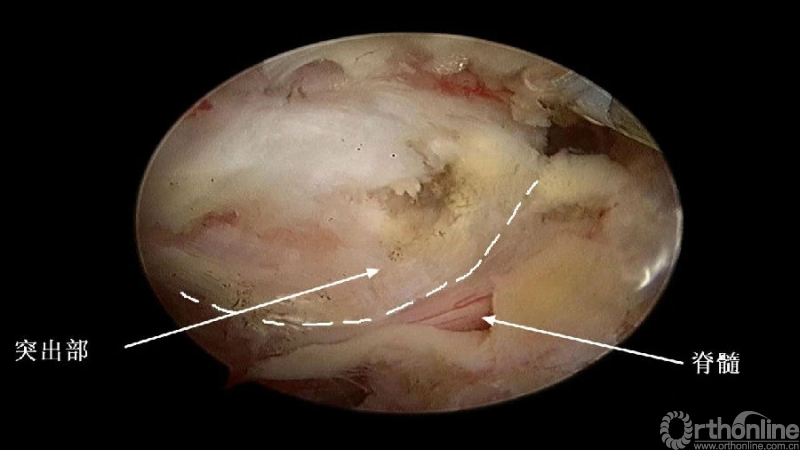

3.从游离骨块的背侧开始,用磨钻将骨块打薄,然后将骨块的底面与脊髓表面仔细分离,将游离骨块摘除;